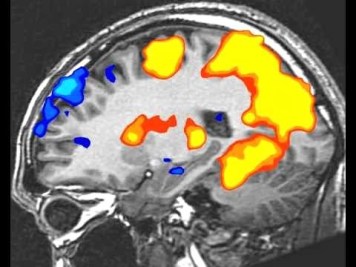

This was partially confirmed by a 2014 study by some German researchers, who tracked the brain activity of both experienced and novice writers using fMRI scanners. Okay, here’s some heavy duty technical stuff I hope you can understand: FMRI (functional magnetic resonance imaging) measures brain activity by detecting changes associated with blood flow. This technique relies on the fact that cerebral blood flow and the activity of neurons in different parts of the brain are coupled.

From You Tube: Brain regions activated by playing Re-Mission. Red/orange/yellow = increased activity. Blue = decreased activity

There were differences in sites of brain activity between the two groups, with the inner workings of the professionally trained writers showing some similarities to people who are skilled at other complex actions, like music or sports. The researchers also found that some regions of the brain became active only during the creative process, but not while copying. When trained writers do mental brainstorming for their stories, some vision-processing regions of the brain became active. It’s possible that the writers were actually ‘seeing’ the scenes they wanted to write. This study has been criticized for the small sample size and for the crudity of the approach, but I find the results compelling and supportive of the results of Baron’s work.